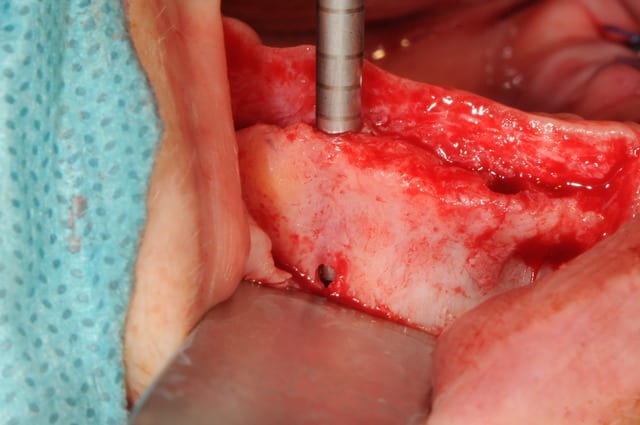

la chir maintenant...

comme l'ensembles des cr^tes étaient fines, j'ai du travailler au plus juste; un premier forage au foret pilote (diam 2mm) et tout le reste aux ostéotomes.

Dsc 6319 lfb3kf - Eugenol

Dsc 6320 uz6tri - Eugenol

Dsc 6321 j0zoen - Eugenol

Dsc 6322 nn01zd - Eugenol

Dsc 6324 dklung - Eugenol

Dsc 6325 c4xggx - Eugenol

Dsc 6326 vrzm0f - Eugenol